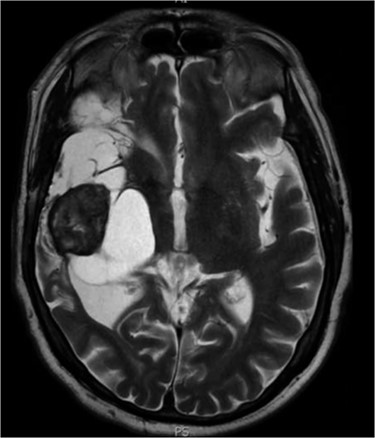

Between 2005 and 2012, the clinical condition remained stable and there were no significant radiological changes identified (Fig. 2). In July 2012, the patient re-presented with worsening left sided weakness and a left sided homonymous hemianopia. CT scan at this time demonstrated a 4 × 4cm well-defined mass of CSF density in addition to the pre-existing lesion in the right external capsule. Neither enhanced with contrast and there was no significant midline shift. An MRI head showed the lesion to contain a significant solid component. It appeared somewhat vascular and there was suspicion that it could represent a low-grade tumour (Fig. 3). The patient underwent a right-sided craniotomy to remove the mass.

Axial MRI head (2012) demonstrating 4 × 4 cm solid mass with surrounding fluid enhancement.